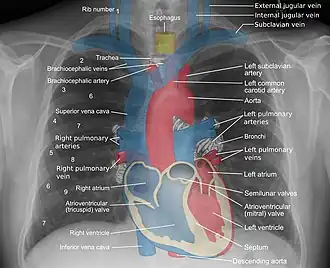

The mediastinum (from Medieval Latin: mediastinus, lit. 'midway';[2]pl.: mediastina) is the central compartment of the thoracic cavity. Surrounded by loose connective tissue, it is a region that contains vital organs and structures within the thorax, mainly the heart and its vessels, the esophagus, the trachea, the vagus, phrenic and cardiac nerves, the thoracic duct, the thymus and the lymph nodes of the central chest.

The mediastinum lies within the thorax and is enclosed on the right and left by pleurae. It is surrounded by the chest wall in front, the lungs to the sides and the spine at the back. It extends from the sternum in front to the vertebral column behind.[3][4] It contains all the organs of the thorax except the lungs.[4][5] It is continuous with the loose connective tissue of the neck.

A number of important anatomical structures and transitions occur at the level of the thoracic plane, including:

- The carinal bifurcation of the trachea into the left and right main bronchi.

- The left recurrent laryngeal nerve branching off the left vagus nerve and hooking under the ligamentum arteriosum between the aortic arch above and the pulmonary trunk below.

- The starting of the cardiac plexus.

- The azygos vein arching over the right main bronchus and joining into the superior vena cava.

- The thoracic duct crossing the midline from right to left behind the esophagus